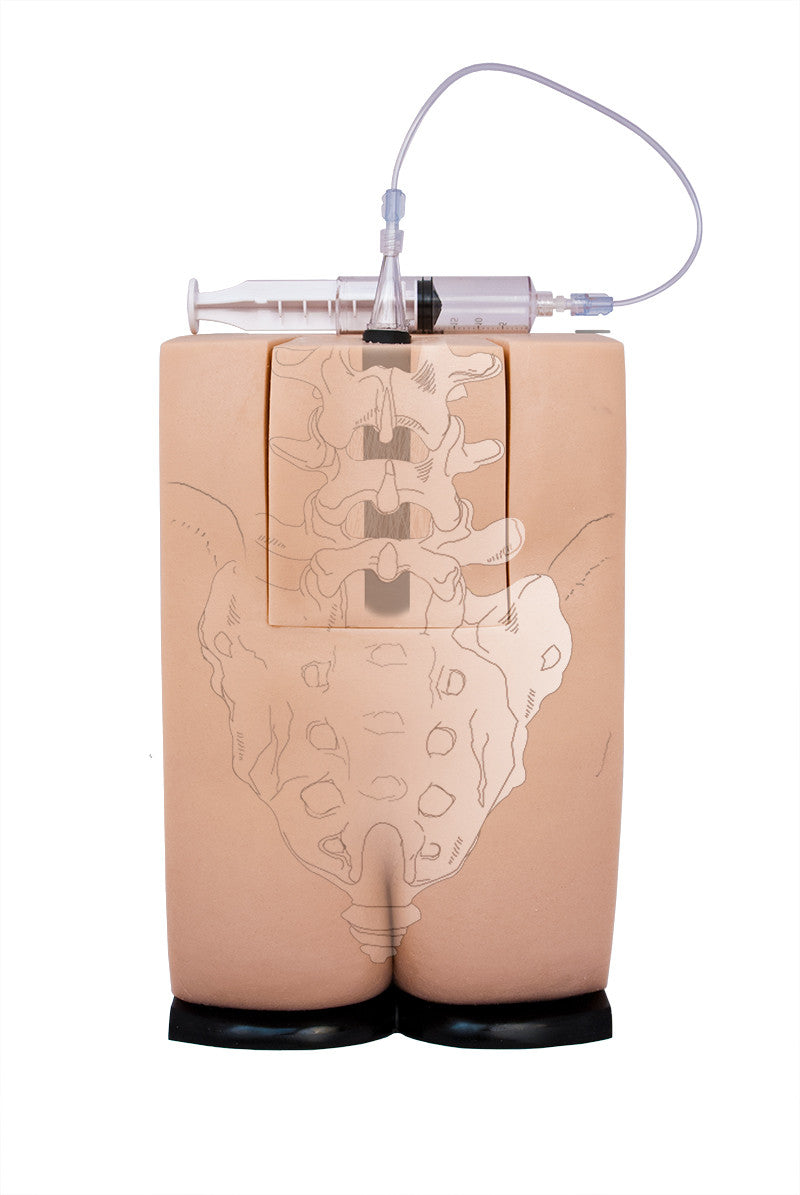

Train students and healthcare professionals in essential epidural injection skills using our highly realistic spine simulators, designed to enhance clinical training and procedural accuracy.

Geriatric LOR Insert (2) for Epidural and Spinal Injection Trainer

Geriatric LOR Insert for Epidural and Spinal Injection Trainer

Replacement Skin for Epidural and Spinal Injection Trainer

Standard LOR Kit (2) for Epidural and Spinal Injection Trainer

Our range of epidural injection trainers includes detailed anatomical models that replicate the lumbar and thoracic spine, providing a hands-on learning experience for anaesthetists, medical students, and pain management specialists. These advanced simulators allow users to practise needle placement, identify key anatomical landmarks, and develop proficiency in administering epidural and spinal anaesthesia with confidence. Ideal for medical schools, hospitals, and professional training programmes, these epidural trainers support skill development in regional anaesthesia, labour pain management, and spinal procedures. With lifelike materials that simulate real patient responses, our models offer a realistic and immersive training experience.